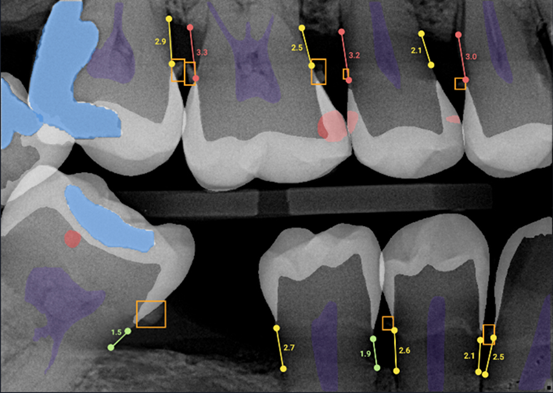

Overjet is the ONLY dental Artificial Intelligence (Ai) FDA-cleared tool that helps your dentist spot cavities, gum issues, and other problems on your X-rays—fast and with incredible accuracy, down to a fraction of a millimeter. The technology uses AI algorithms that have been trained on millions of dental radiographs to distinguish between various findings such as caries, infections, and root canal treatments. Dentists have rated Ai-enhanced images as approximately 25% higher quality compared to original radiographs.

FDA‑cleared to detect and outline decay (“caries”), detect calculus, and bone measurements—a distinction not shared by any other Ai dental product.

At Iconic Dental Arts, we're thrilled to introduce Overjet. The system highlights your X-rays with colored highlighting and precise measurements to clearly illuminate any diseases, conditions, or areas of concern. These clear visual representations of your oral health conditions, provide effective patient education and personalized treatment planning.

Our dental professionals possess years of specialized training to interpret imaging results, enabling them to identify decay, cavities, and other oral health issues within your X-rays. For patients without this extensive background, these findings can be challenging to understand, even when dentists carefully explain their observations. Now you can clearly understand your care and feel confident in your treatment plan.